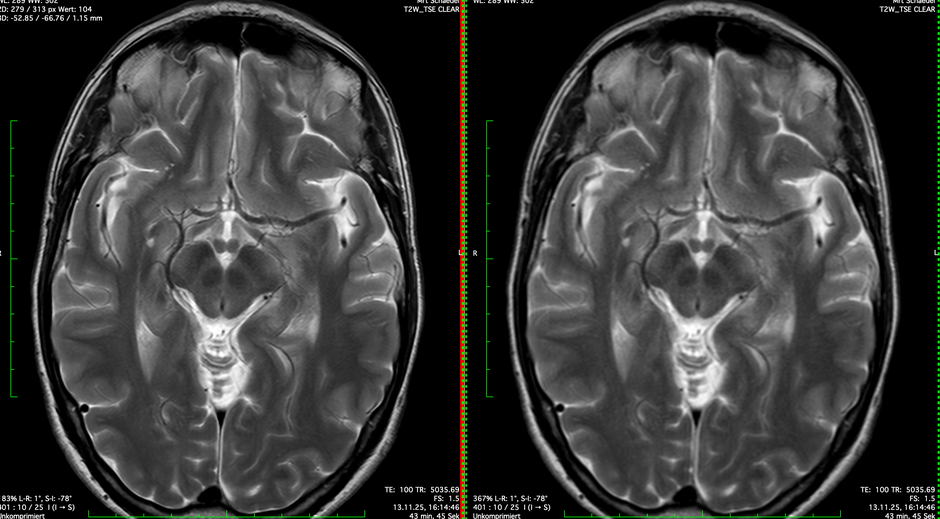

Ab sofort können wir im MRT die Bilder schneller erstellen und sparen bei deutlich verbesserter Bildqualität erst 33%, in kürze bis zu 60% Untersuchungsdauer ein. Dies gelingt bei der extrem guten Homogenität des Magnetfelds in unseren Kernspintomografen.

Wir können gleichzeitig durch neue Untersuchungstechniken auch Bewegungsartefakte verhindern.

Neben der KI hilft hier auch einfach der Einsatz von Physik und Intelligenz.

MRT des Gehirns. Links mit KI. Rechts ohne KI.